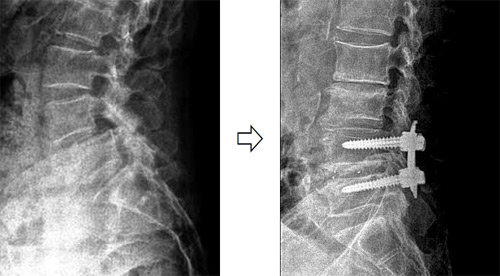

- 수술 고려: 신경 손상이 심하고 보존적 치료에 반응이 없을 때만 고려